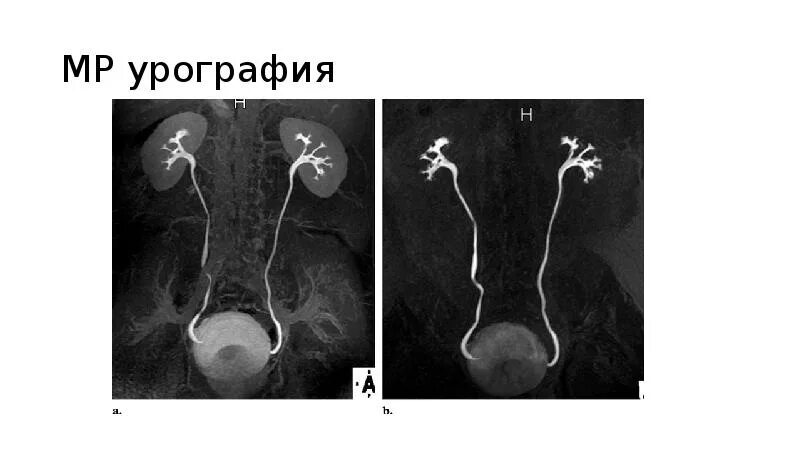

После урографии